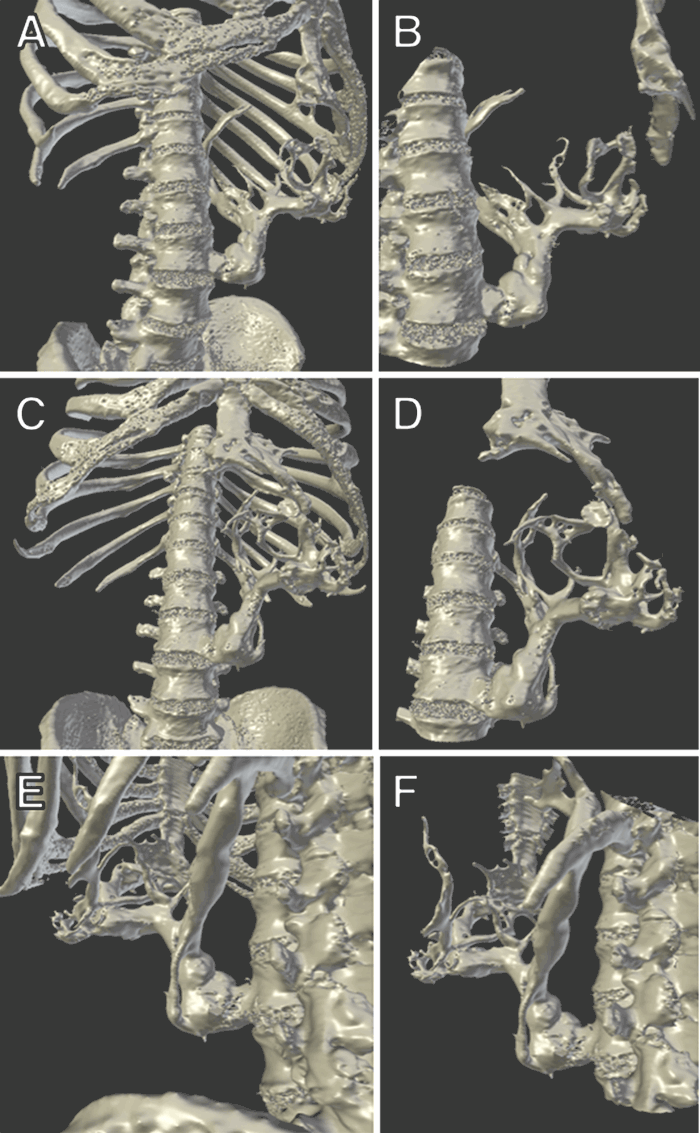

Several years later, the patient reported a three-day period characterized by diffuse abdominal pain, anorexia, nausea, vomiting, and no bowel movements. Upon arrival to the tertiary care center, the patient endorsed persistent abdominal pain. On physical exam, his abdomen was diffusely tender in all quadrants and high-pitched bowel sounds were present. A CT scan of the abdomen and pelvis with IV contrast demonstrated a focal segment of small bowel dilated to 4.4 cm, with a discrete transition point consistent with SBO (Figure 1). The CT also revealed an osseous projection arising anteriorly from the L3 vertebral body that joined with an osseous projection from the inferior left T12 rib and formed a pseudoarthrosis in the abdomen from a third projection—this third projection arose from the sternum/xiphoid process (Figure 2 and Figure 3) This finding was suggestive of trauma-related heterotopic ossification (HO)—indeed, this ossification wrapped around the small bowel (Figure 1A) and provided a clear potential for obstruction. A ventral hernia was also noted on imaging but did not appear to be the cause of the patient’s SBO. The patient was unaware of the ossification and denied chronic abdominal pain that might be related to the ossification.

Figure 2. Representative axial (A), multilayer coronal (B), and multilayer sagittal (C) CT images of the abdomen, demonstrating abdominal heterotopic ossification arising from the L3 vertebral body and extending into the anterosuperior abdomen (black arrows).

Figure 3. Three-dimensional reconstruction of the CT in Figures 1 and 2 demonstrating abdominal heterotopic ossification arising from the anterior L3 vertebral body and joining an osseous projection from the inferior left T12 rib and another projection from the sternum in a patient with a distant history of a stab wound to the posterior left back. The reconstruction is observed from the right anterolateral (A), anterior (C), and left inferolateral (E) views. Simplified reconstructions with the surrounding normal osseous structures removed are presented from the right anterolateral (B), anterior (D), and left inferolateral (F) views.